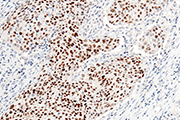

Ki67 antibody (Cat#: 100130-MM19)

Immunochemical staining of human Ki67 in human lung cancer.

Immunochemical staining of human Ki67 in human lung cancer. Image Credit: Sino Biological Inc.